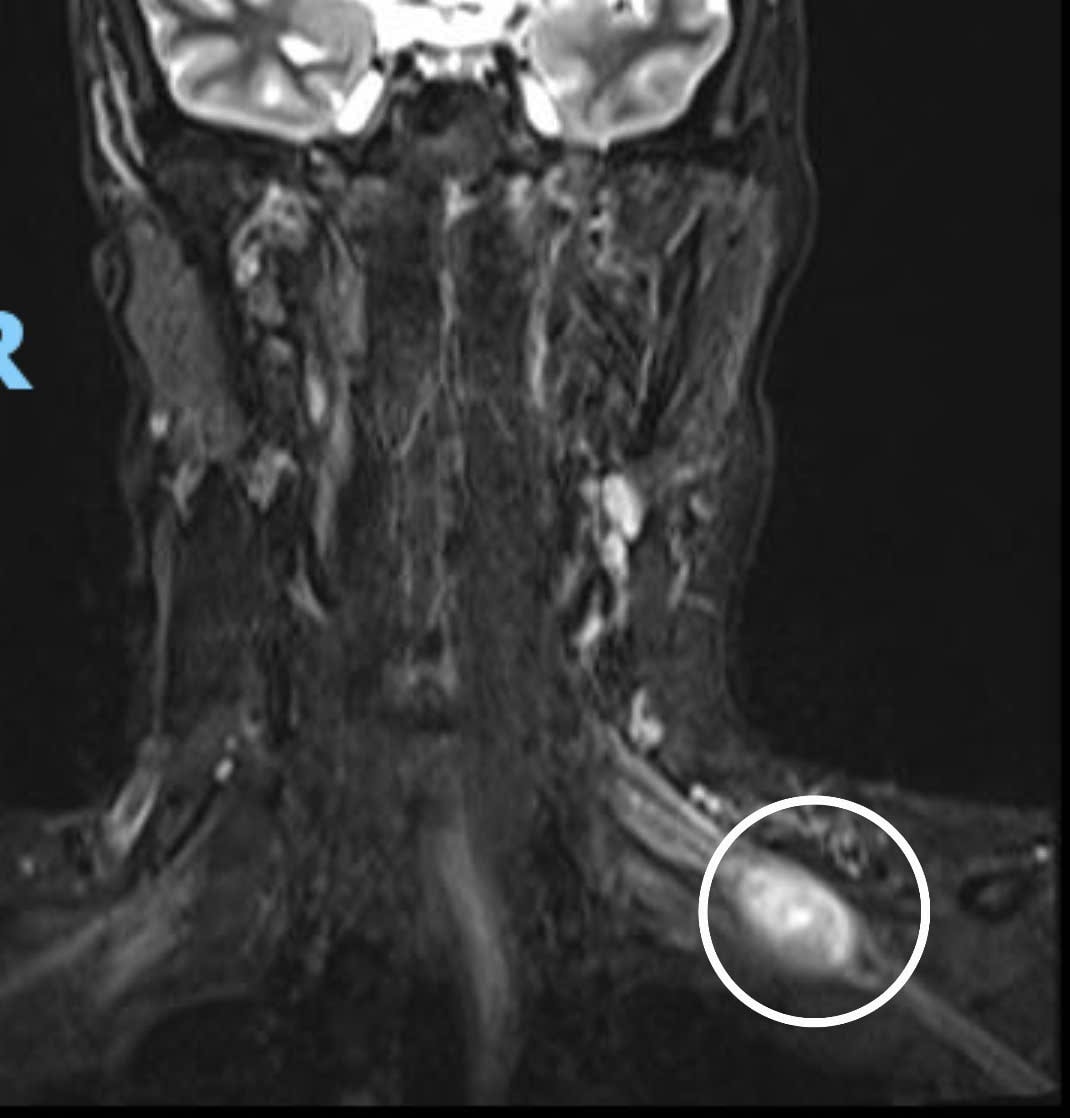

Раніше пацієнтка Хьюїнь Тан Тхань (33 роки) звернулася до онкологічної лікарні Да Нанга на обстеження зі скаргами на утворення в лівій надключичній ділянці, яке було м’яким на дотик та мало обмежену рухливість. Ультразвукове дослідження показало гіпоехогенне ураження розміром приблизно 32x21 мм, яке було важко відокремити від сусіднього плечового сплетення. Крім того, на зображенні МРТ з контрастуванням пухлина м’яких тканин лівої підключичної області мала ознаку «щурячого хвоста», характерну для доброякісної шванноми.